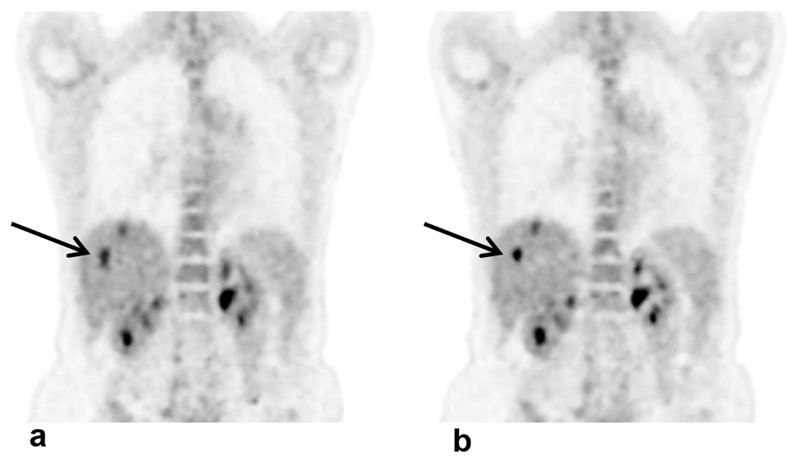

也有团队在用机器学习提升医学影像的成像速度和质量。照过X光片的人,可能记得,医生会让病人屏住呼吸。这样做的目的,是为了防止呼吸运动影响成像。X光成像只需几秒钟,但正电子发射计算机断层扫描(PET)通常要进行十几分钟,就不是屏住呼吸能解决的了。目前很多研究团队,通过自动门控技术,修复呼吸对PET成像的影响。

►原始PET成像(a)和使用自动门控技术纠偏过的PET成像(b),(b)图的伪影更少了。图片来源:Walker et al. 2018。